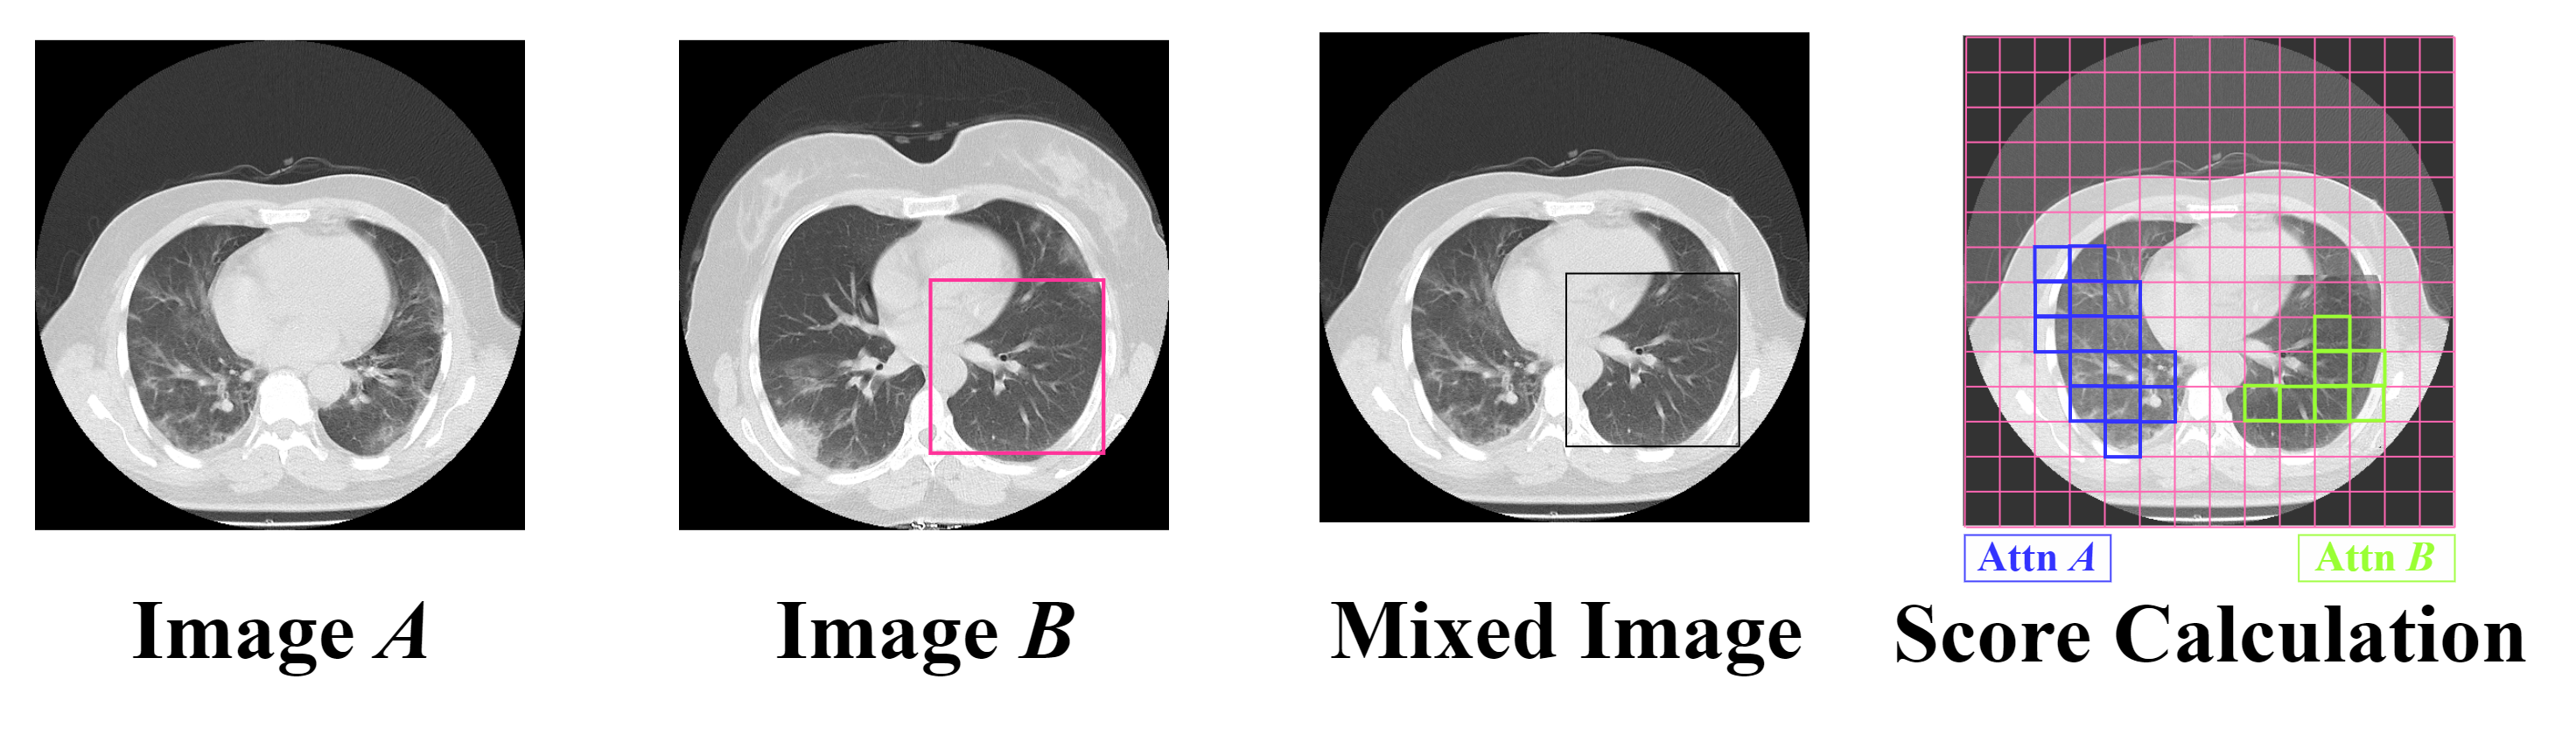

3.2 Data Augmentation: Conditional Online TransMix

In our work, we have addressed the problem of score imbalance in pneumonia severity infection datasets by using an online augmentation technique based on the TransMix method [13]. Although this technique was originally proposed for classification tasks, we have adapted it for regression by generating new mixed scores for the newly mixed images. Our novel adaptation of this data augmentation technique leverages attention maps to drive the score mixing process. The mixed image is obtained using the traditional CutMix method [60], where a random patch of image is inserted into image to form a new mixed image, as shown in Figure 3. After creating the mixed image, its relative ground truth score is calculated following the TransMix approach. This method assigns mixed labels based on a multi-head class attention map computed using self-attention mechanisms similar to those used in ViTs. The class attention map of the augmented image represents the attention of the class token (CLS) to the input patches of the mixed image and highlights the most useful patches of the input image for the final prediction.

TransMix uses this attention map to control the process of mixing scores. In this context, (representing the proportion of the source image) is set to the sum of the weights in the attention map that overlaps with the clipping mask, each weight corresponding to the importance assigned to a particular region of the image.

Given images and , we update the mixing coefficients using the attention map of the mixed image :

| (4) |

where represents nearest-neighbor interpolation that downsamples the mask from into pixels.

In this way, we can dynamically reassign the weights of the scores depending on how much attention map is directed to each patch. The patches that receive more attention have a higher proportion of the [13]. The ground truth score of the mixed image is:

| (5) |

where and are the ground truth scores of images and respectively.

In our implementation, TransMix was applied conditionally to address dataset imbalance by focusing on underrepresented scores. We specifically performed TransMix augmentation on images with these scores, ensuring the augmented samples enhanced the representation of the low-distribution regions. The decision to apply augmentation was based on a threshold derived from the training dataset’s score distribution. By defining a threshold for the ground truth score of the image, the network effectively learned to generate new images and their corresponding labels, improving its ability to generalize from a more balanced and diverse set of training examples. This approach led to better generalization and more accurate severity predictions.